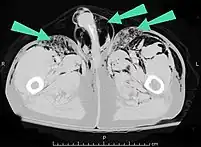

Significant cases of subcutaneous emphysema are easy to diagnose because of the characteristic signs of the condition.[1] In some cases, the signs are subtle, making diagnosis more difficult.[13] Medical imaging is used to diagnose the condition or confirm a diagnosis made using clinical signs. On a chest radiograph, subcutaneous emphysema may be seen as radiolucent striations in the pattern expected from the pectoralis major muscle group. Air in the subcutaneous tissues may interfere with radiography of the chest, potentially obscuring serious conditions such as pneumothorax.[18] It can also reduce the effectiveness of chest ultrasound.[27] On the other hand, since subcutaneous emphysema may become apparent in chest X-rays before a pneumothorax does, its presence may be used to infer that of the latter injury.[13] Subcutaneous emphysema can also be seen in CT scans, with the air pockets appearing as dark areas. CT scanning is so sensitive that it commonly makes it possible to find the exact spot from which air is entering the soft tissues.[13] In 1944, M.T. Macklin and C.C. Macklin published further insights into the pathophysiology of spontaneous Macklin's Syndrome occurring as a result of a severe asthmatic attack.